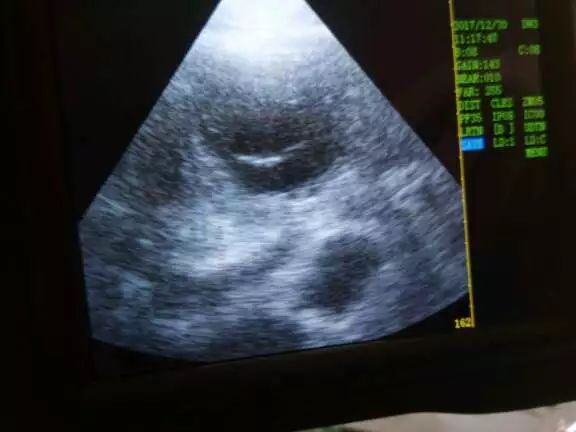

给母猪测孕为猪妊娠21天左右为最佳,设备开启预热后,务必在探头顶端涂上适量的耦合剂(超声波诊断专用密封剂,有利于探头与皮肤的充分接触),将探头与猪的皮肤贴紧,在孕检部位小角度移动,观察设备屏幕,看有没有明显的黑点或带有空洞的黑圈,判断是否妊娠。探头接触猪的皮肤之前必须确认皮肤上是否有脏物,如有脏物会影响诊断结果。

(上图为客户实际操作反馈)

四、图像诊断

1、在B超屏幕上,我们看到是黑色,这表示探测到的是低密度的液体性的物质,比如:膀胱里的尿液,子宫里的羊水,卵泡里的卵泡液,盆腔壁血管里的血液,等等。

2、在B超屏幕上,我们看到是白色,这表示探测到的是高密度的组织或器官,比如:胎儿的骨骼,子宫角内膜、肌肉层的增生,卵巢表面沉积的脂肪,持久黄体,等等。

3、在B超屏幕上,我们看到的是灰色,这表示探测到的是中等密度的组织或器官,比如:子宫角的肌肉组织,胎儿的肌肉组织,周期(有腔)黄体,等等。